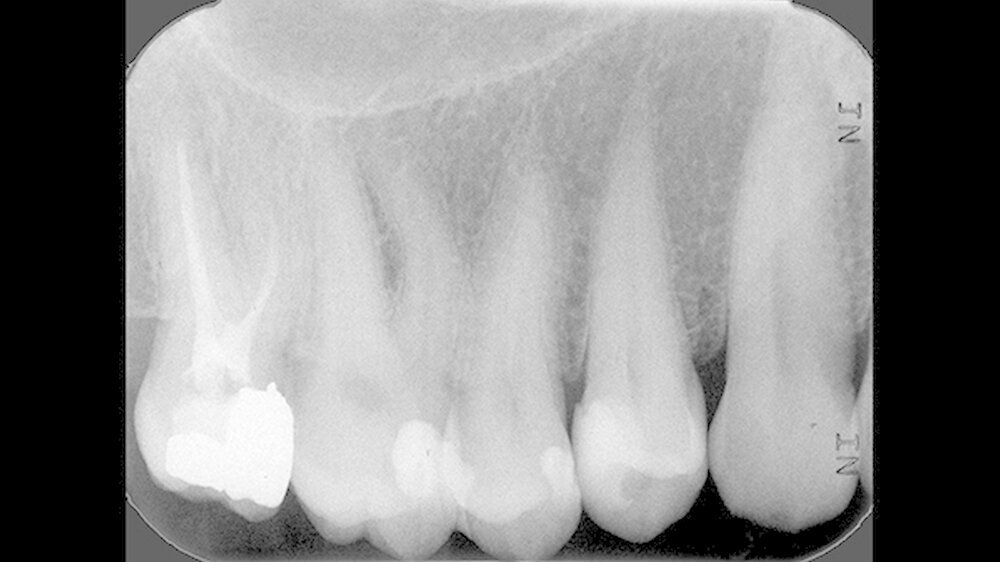

Ein 43-jähriger Patient stellte sich zur Routinekontrolle in der Poliklinik für Zahnerhaltung des Universitätsklinikums Münster vor. Die allgemeinmedizinische Untersuchung zeigte keine Besonderheiten. Sowohl der klinische zahnmedizinische Befund als auch die angefertigte Röntgenaufnahme deuteten auf eine Approximalkaries distal an Zahn 14 hin (Abbildungen 1 und 2). Daher wurde der Patient auf die Notwendigkeit einer Füllungstherapie hingewiesen.